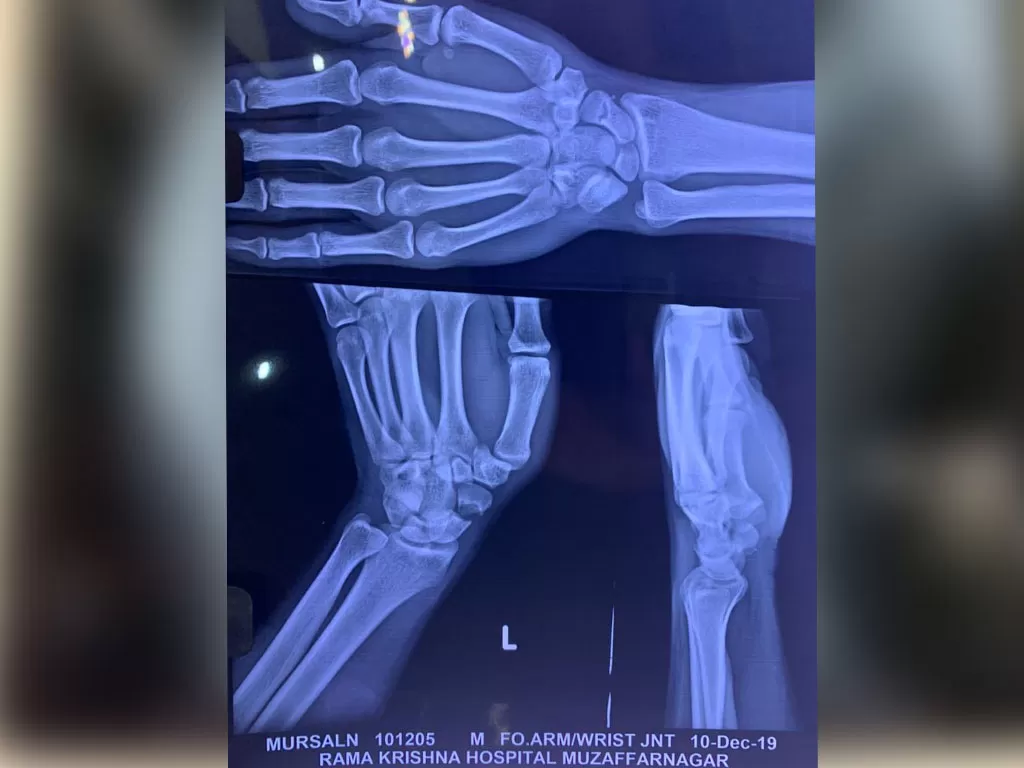

Mr. Marsaln

Name: Mr. Marsaln

Date of Operation: 10 Dec 2019